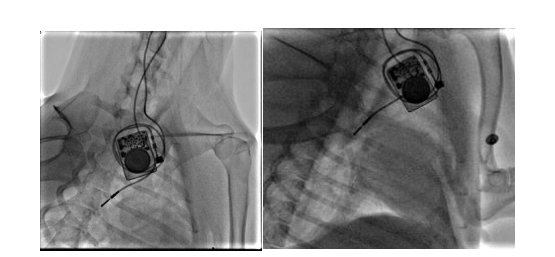

團(tuán)隊構(gòu)建犬的慢性房顫動物模型,分析無創(chuàng)體表心電標(biāo)測和有創(chuàng)心外膜心電標(biāo)測系統(tǒng)采集的心電信號的相關(guān)性。我們通過經(jīng)頸靜脈介入(圖10)和右外側(cè)開胸小切口(圖11)兩種方法建立快速起搏右心房的犬慢性房顫模型

圖9 經(jīng)頸靜脈介入路徑構(gòu)建右心房快速起博犬的慢性房顫模型

圖10 經(jīng)右側(cè)胸部小切口構(gòu)建右心房快速起搏犬的慢性房顫模型

研究結(jié)果證明了我們的128導(dǎo)聯(lián)體表電位標(biāo)測系統(tǒng)采集房顫電位信號的可靠性。